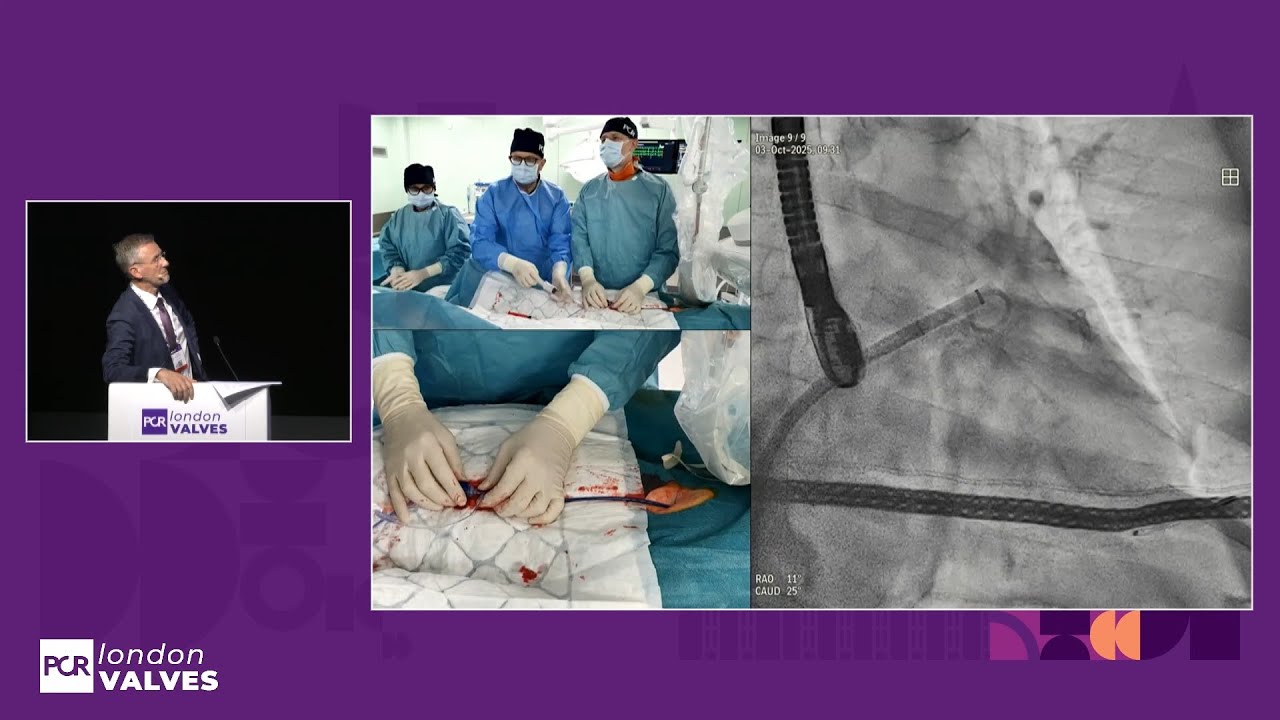

TAVI for bioprosthetic valve failure: LIVE Educational Case from Institut Cardiovasculaire Paris Sud - Massy, France